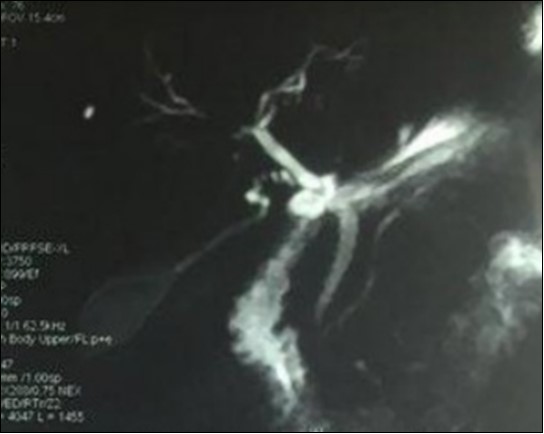

We report the case of an asymptomatic 49 years old male patient, in which a routine check objectified a biological cholestasis (gammagmutamytransferase = 2-3N and ALP = 5-6 N without hyperbilirubinemia or cytolysis). Nos past medical facts were noted. Abdominal ultrasound, viral markers and antibodies measurement (Ac Anti-nuclear, anti-Mitochondrial, anti-LKM1, Anti-cytoplasmic) were normal. Magnetic resonance choalngiopancreatography objectified multiple biliary strictures and parietal irregularities evocative of SC (Figure 1). Colonoscopy showed no associated inflammatory bowel disease. Patient received high doses of ursodeoxycholic acid (20mg/kg) for the SC with partial improvement of liver function but persistence of a marked rise in ALP level. In order to better characterize the nature of ALP, a dosage of ALP isoenzymes was performed and objectified a predominant bone fraction (83%), while liver fractions H1 and H2 were respectively of 12% and 4%. X rays objectified bone condensations with a fibrillar appearance and bone hypertrophy suggestive of PD (Figure 2). A bone scan made for lesions mapping showed a multifocal PD (Figure 3). The patient was treated by bisphosphonates (injections of zoledronic acid), which was associated with a decreasing in ALP level after 6 months.

Figure 1.Magnetic resonance cholangiopancreatography showing multiple biliary strictures and parietal irregularities

Magnetic resonance cholangiopancreatography showing multiple biliary strictures and parietal irregularities